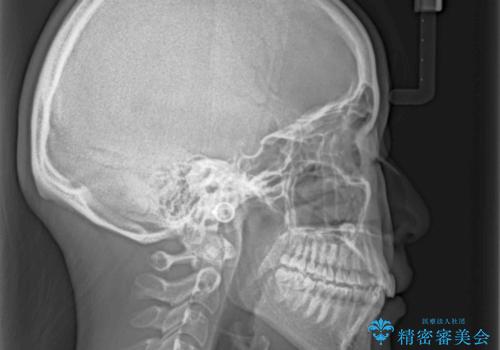

- 前歯のデコボコと残っている乳歯の部分へのインプラント治療を希望して来院された患者様です。

当初は目立たない上下裏側矯正を希望されていましたが、歯並びの悪さによる磨き残しが多く、歯肉炎が認められたため、より清潔な環境で治療を進められるインビザラインを選択することとしました。

また、インプラント治療については、インビザラインによる矯正治療中の最適なタイミングで治療を行い、治療期間の短縮を図ることとしました。